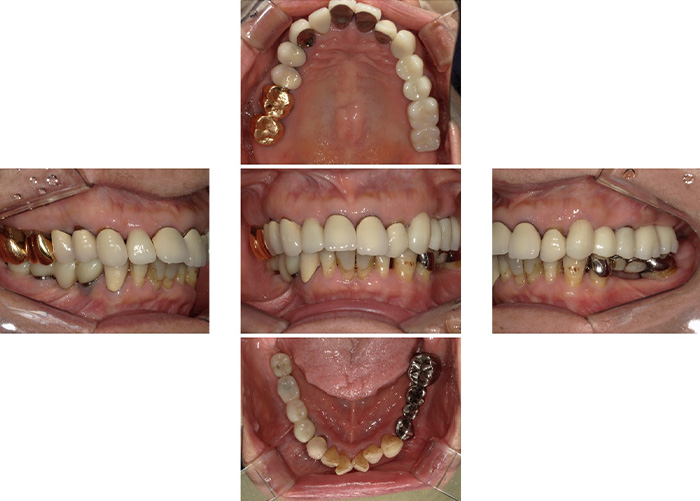

Case.03

![]() ![]() |

|---|

| 主訴 | 上の歯が全部ぐらぐら動く |

|---|---|

| 治療期間 | 12か月 |

| 治療費 | 3,000,000円(税込3,300,000円)(ALL ON 4) |

| 治療内容 | 4本のインプラントで上の歯をすべて補う治療法です。 抜歯をしたその日に仮歯を入れることも可能です。 |

| 治療のリスク | 一時的な鼻出血、内出血、眼出血、上顎洞炎、腫脹のリスクがあります。 |